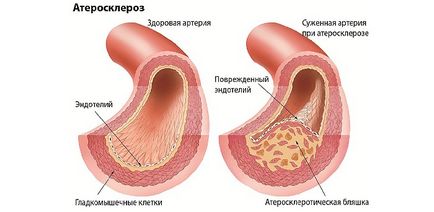

Érelmeszesedést. Alapvetően ez a betegség befolyásolja az artériák minden méretben, ami a kialakulásához is. Koszorúér ateroszklerózis kialakulásához vezet a szívkoszorúér-betegség. Győzd cerebrovascularis - encephalopathia, vagy a fejlődés a ischaemiás stroke.